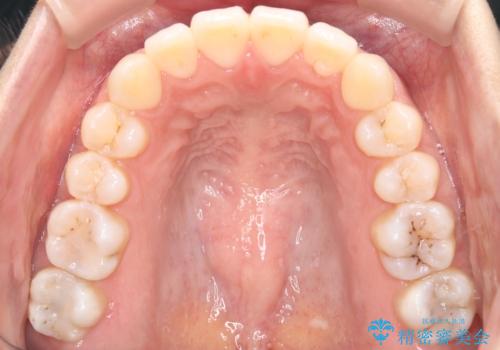

【ワイヤー矯正】前歯の突出感、下の歯の並びを良くしたい

- 主訴:上の前歯の突出感と下の歯の並びを改善したい

非抜歯で矯正治療を行った場合と、上下左右4番目の歯を抜歯して矯正治療を行った場合のシミュレーションを見ていただき、非抜歯での矯正治療を希望されました。

非抜歯にて矯正治療を行いました。

IPRを行い、前歯部の突出感の改善に努めました。

期間:1年9カ月